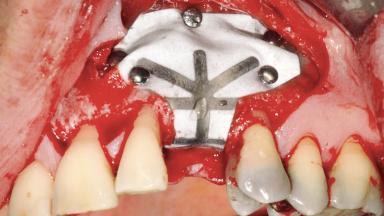

Guided Bone Regeneration (GBR) with a Particulated Autologous Graft and a ePTFE-Reinforced Membrane for Vertical Augmentation of a Single-Tooth Edentulous Space in the Esthetic Zone

A 47-year-old Caucasian woman with a single-tooth edentulous space at the site of the left maxillary canine was referred for treatment. She had undergone traumatic extraction of this impacted canine several months before referral. Her chief complaint was the dissatisfying appearance of her smile. The patient desired a stable and esthetic rehabilitation of the site. Her dental history showed no evidence of periodontal disease or bruxism. She had no systemic diseases, was not taking any medications, and did not smoke. The extraoral examination revealed a high lip line and an inadequate soft-tissue volume at the defective canine site. Large black triangles were visible between the canine and its adjacent teeth.

| Bone Augmentation | Staged|Vertical |

| Augmentation Materials | Autogenous chips|Membrane |

| Bone Volume | Deficient vertically or deficient vertically AND horizontally |